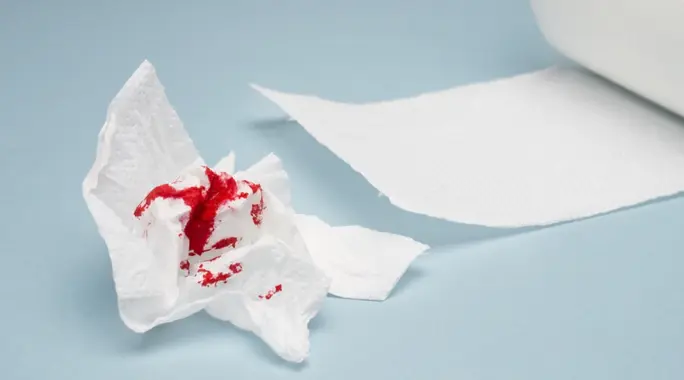

نزيف البواسير تجربة مزعجة وشائعة تؤرق الكثيرين. بينما تعد البواسير حالة منتشرة، فإن رؤية الدم يمكن أن تكون مقلقة حقًا. لحسن الحظ، هناك العديد من طرق علاج نزيف البواسير التي يمكن أن تساعدك في استعادة راحتك وتجنب المضاعفات. سواء كنت تبحث عن حلول منزلية بسيطة أو علاجات طبية متقدمة، سنقدم لك دليلاً شاملاً لفهم خياراتك والتعامل مع هذه المشكلة بفعالية.

تحدث البواسير عندما تلتهب الأوردة في فتحة الشرج والمستقيم وتنتفخ. يمكن أن يسبب هذا الالتهاب الألم والحكة وأحيانًا النزيف. غالبًا ما ينجم نزيف البواسير عن تلف أو تهيج جدران هذه الأوعية الدموية المتورمة.

في كثير من الحالات، يتوقف النزيف من تلقاء نفسه، خاصةً إذا كانت البواسير بسيطة. ومع ذلك، قد تتطلب الحالات الأكثر شدة أو النزيف المستمر تدخلاً لـ علاج نزيف البواسير ومنع تفاقم المشكلة أو حدوث مضاعفات.